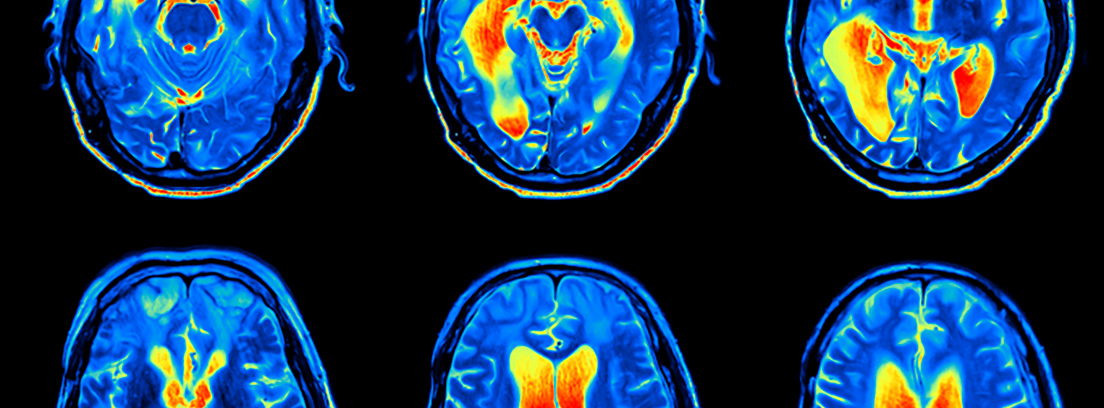

Las exploraciones complementarias incluyen inicialmente un análisis de sangre con glucosa, un electrocardiograma, la saturación de oxígeno en sangre, la temperatura axilar y la realización de un TAC craneal urgente.

El TAC craneal es la técnica de elección en todo enfermo con un déficit neurológico de instauración aguda. Permite descartar ictus hemorrágicos, así como lesiones cerebrales no vasculares como tumores o hematomas. Otras pruebas a realizar en función de la sintomatología del paciente, son:

- RMN cerebral